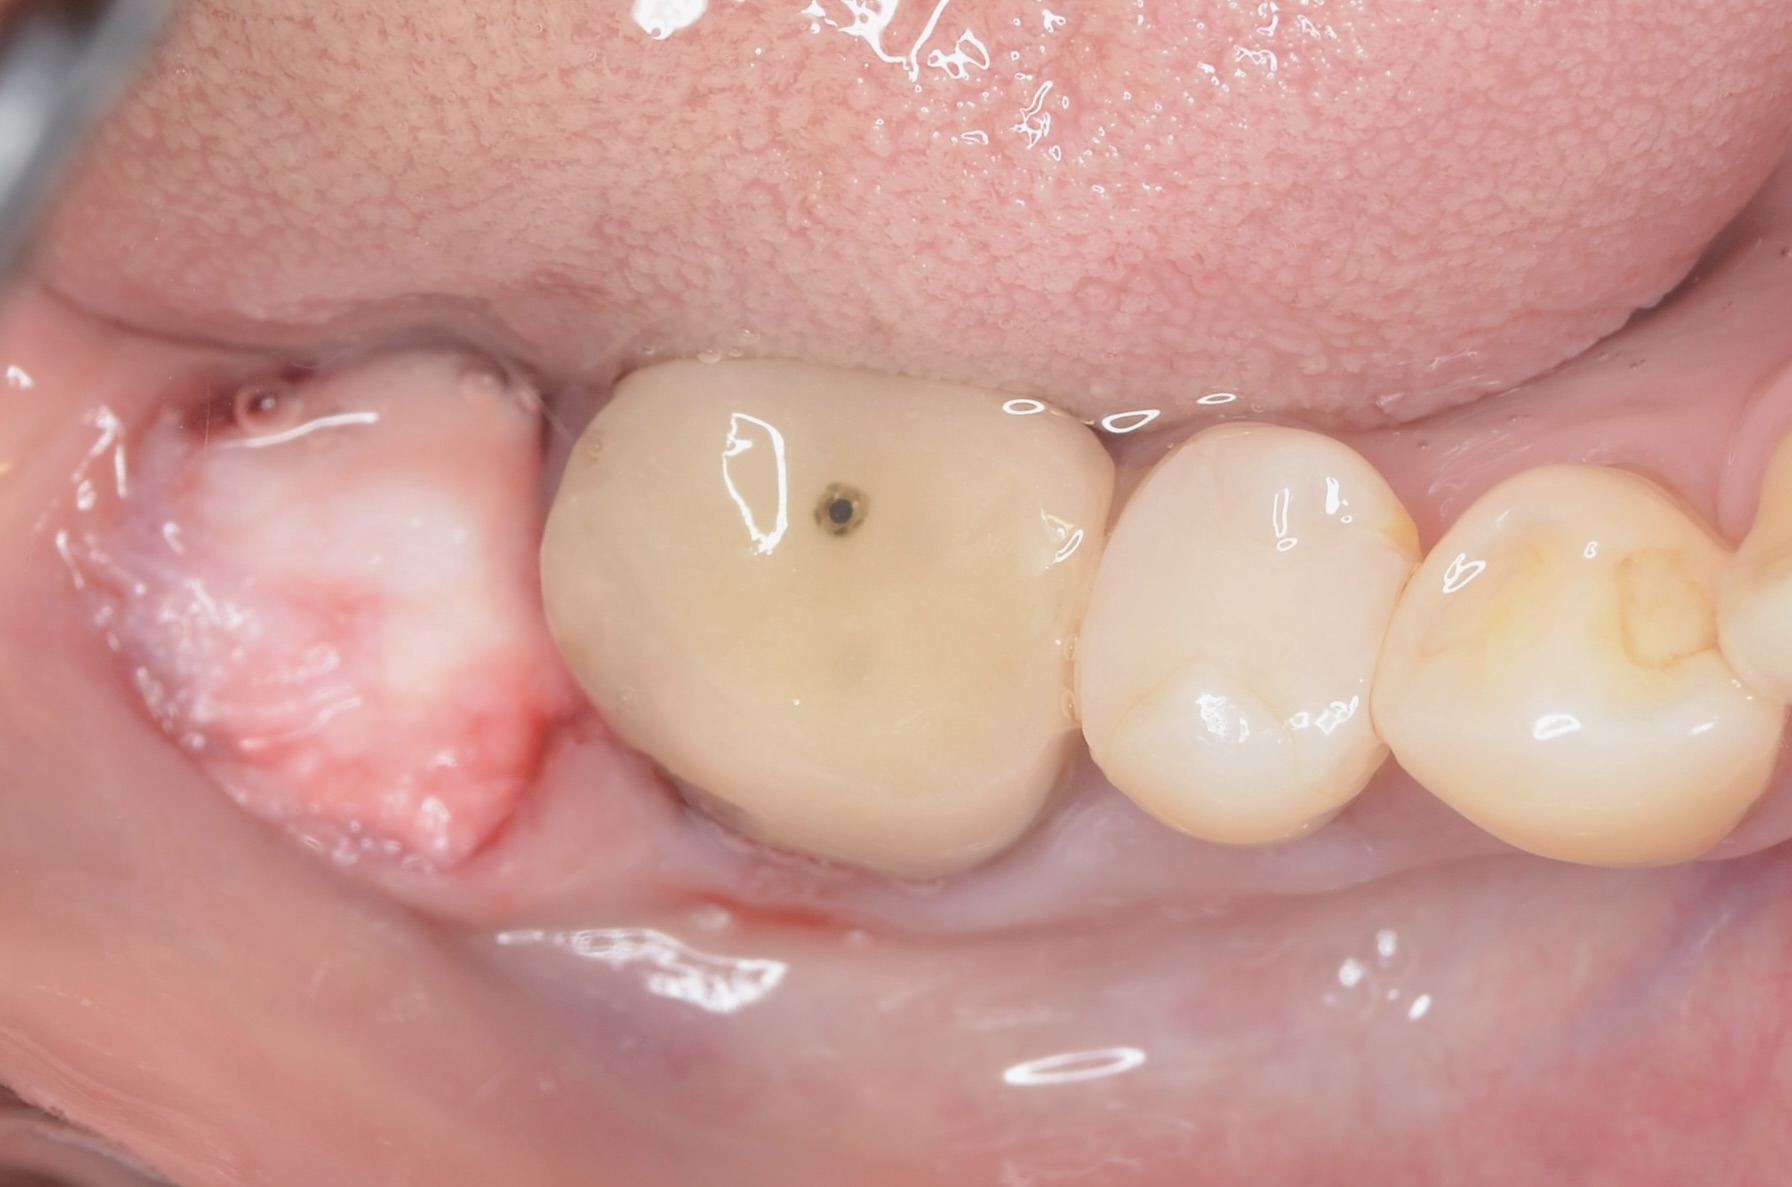

ジルコニアクラウン

綺麗に補綴できました。 -